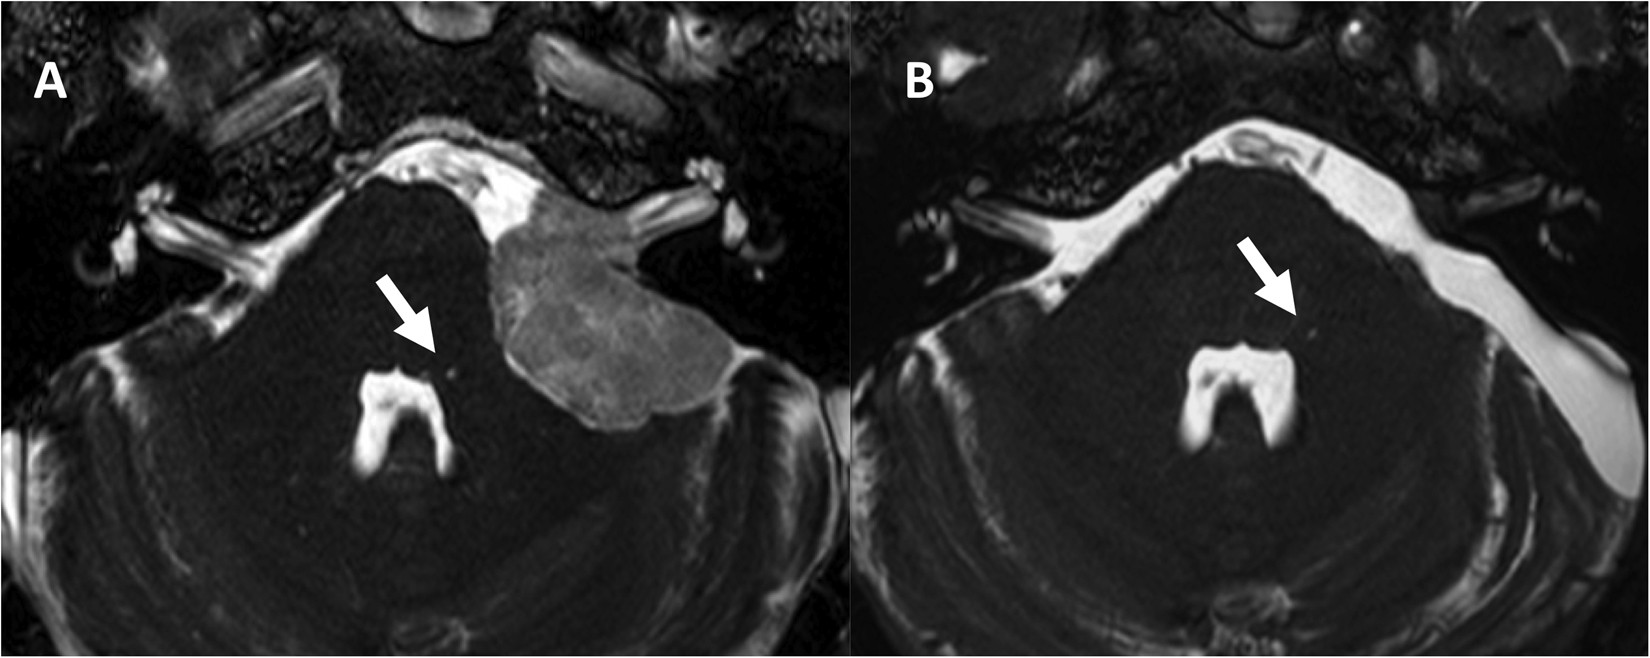

Figure 4

Representive preoperative Gd-enhanced b-FFE MR image of the FHI (arrow) in a patient with cerebellopontine angle meningioma (A). Postoperative (B) b-FFE image shows complete resection of tumor and no signal change of FHI (arrow).